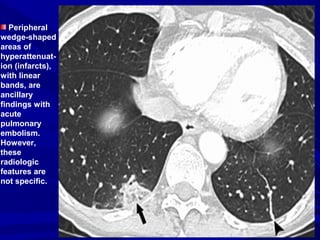

Peripheral

wedge-shaped

areas of

hyperattenuat-

ion (infarcts),

with linear

bands, are

ancillary

findings with

acute

pulmonary

embolism.

However,

these

radiologic

features are

not specific.